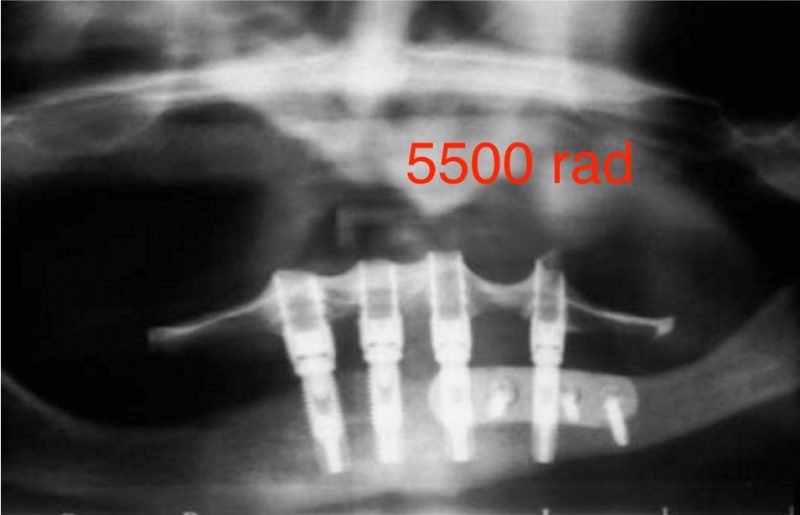

Een patiënt met de ziekte van Parkinson door Dr Defrancq aldus behandeld. De implantaten werden geplaatst onder lokale verdoving en de tanden werden er enkele dagen later vast opgeschroefd .